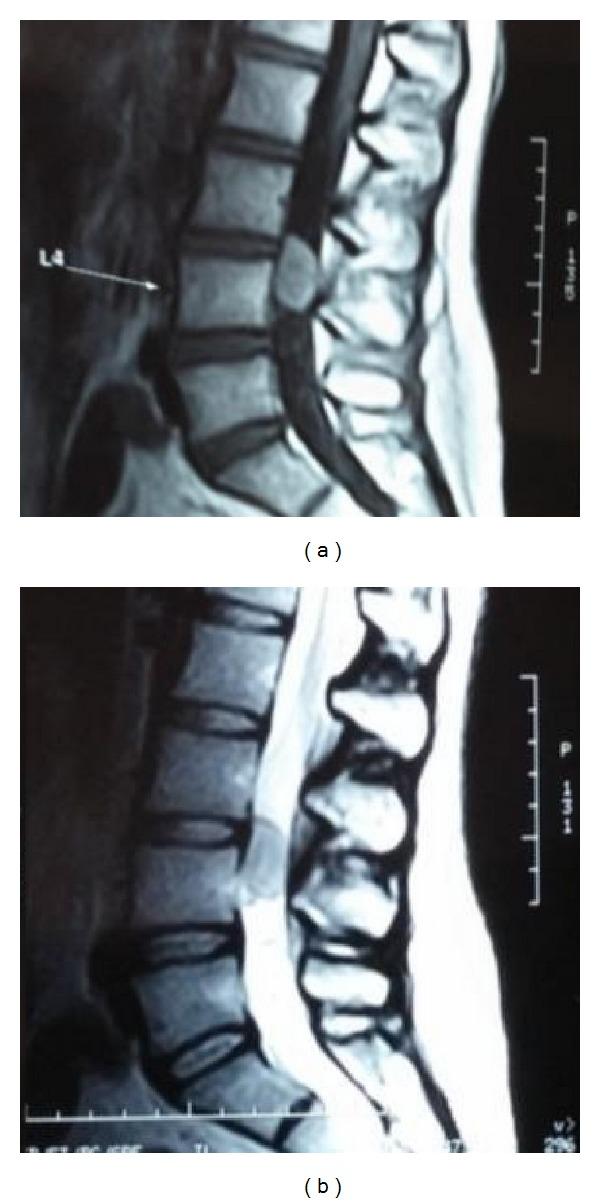

Solitary fibrous tumor (SFT) is a rare neoplasm occurring in the central nervous system. It rarely occurs in the spine. This paper reports the fifth case of SFT in a 34-year-old female and focusses on differential diagnosis and importance of surgical treatment.

孤立性纤维瘤(SFT)是一种发生于中枢神经系统的罕见肿瘤。它很少发生于脊柱。本文报道了一例34岁女性的第五例SFT病例,并着重探讨了鉴别诊断及手术治疗的重要性。